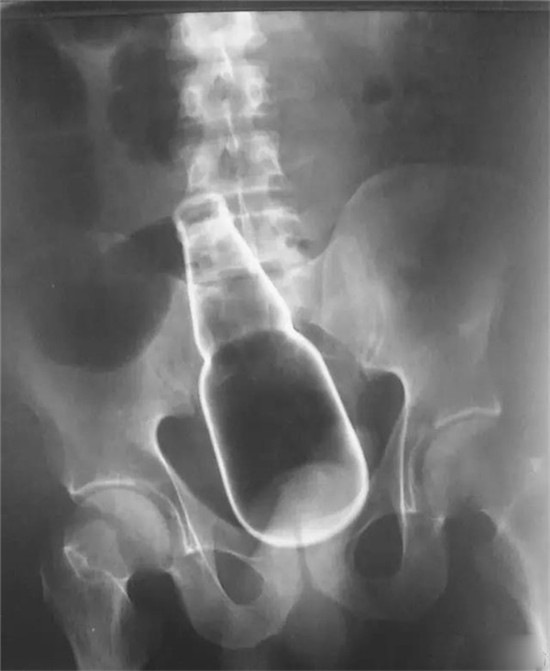

医生给他检查的时候,发现已经有腹膜炎症状,怀疑肠梗阻,拍了个片子,就是上面那个片子:一条大黄鳝在肚子里。

考虑到他已经有腹膜炎的症状,说明肠子已经有个地方破了。只能动手术了。

把肚子打开后,发现大肠破了个洞,黄鳝的头,就在那个洞里。他肚子里都是大便。他的肠子水肿很厉害。黄鳝堵住了大肠,肠梗阻,导致大肠坏死穿孔了。

这种情况下,就是把大肠的洞补起来,洞也长不好。只能造瘘了。也就是在破了个洞的地方把大肠割断,肚皮上挖个洞,大肠拖到肚皮外面,以后的大便从肚皮上排出来。等肚子里炎症消退后,再把大肠放回肚子里接回去。这样他要动2次手术。

就这样,他死里逃生了。

上面是前几年一名患者大肠里的黄鳝。

这条黄鳝还是雌性的黄鳝,你知道我怎么看出来的吗?